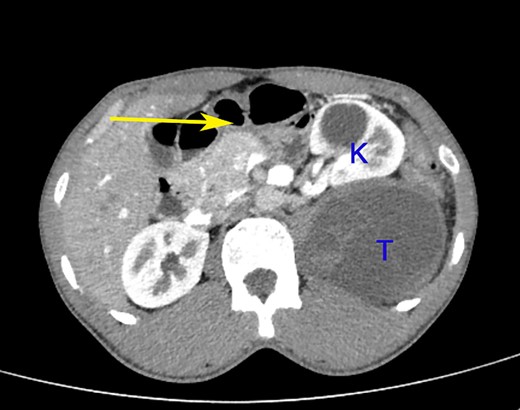

A man in his 30s presented with symptoms suggestive of irritable bowel symptoms with increased bowel movements coinciding with the onset of colicky abdominal pain for the past 8 months. The bowel movements relived his pain and had no remission from his symptoms. He had no relevant medical comorbidities in the past. The patient had normal vitals. There were no physical exam abnormalities except for a slight fullness in the left renal angle (Fig. 1). There was nothing significant on a rectal examination. An X-ray of the chest showed normal findings. Blood investigations showed: haemoglobin 130 g/l, total leukocyte: 7.4 × 109/l, serum creatinine 0.52 mg/dl, fasting blood sugar 90 g/dl, alanine transaminase 26 U/L, aspartate transaminase 42 U/L, alkaline phosphatase 32 U/L and total bilirubin 0.8 mg/dL. Ultrasonography showed a 10-cm mass, with mixed echogenicity. Posterior to the left kidney. Colonoscopy was normal. An abdominal CT scan showed a paravertebral tumour with peripheral enhancement and heterogenous contrast within the tumour (Fig. 2). The tumour showed high intensity on a T2-weighted MRI (Fig. 3). The left kidney and colon were displaced anteriorly. Fine-needle aspiration biopsy was inconclusive. The clinical diagnosis was a retroperitoneal schwannoma. On laparotomy, the left colic vessels appeared to be splayed by the tumour (Fig. 4). The tumour 11 × 6 × 3 cm3 (Fig. 5), which seems to be arising from the L2 nerve, was resected completely (Fig. 6). The patient had no sensory or motor loss postoperatively. He was discharged without complications on the 10th postoperative day. His colonic symptoms had disappeared after surgery. The gross appearance of the resected tumour showed cysts and haemorrhage patches (Fig. 7). Histopathology showed areas of hypercellularity (Antony A) and hypocellularity (Antony B) with degenerative changes leading to nuclear atypia and cystic spaces, typical of an ancient schwannoma (Figs 8–11). Immunohistochemistry with S-100 was positive (Fig. 12). He was devoid of digestive symptoms or radiological evidence of recurrence at 12 months.

A contrast-enhanced CT scan of the abdomen at the level of the L2 vertebra shows a paravertebral tumour (T) posterior to the kidney (K). The tumour shows peripheral enhancement and inhomogeneous intra-tumoural contrast enhancement. The left colon is pushed to the right and anteriorly (arrow).